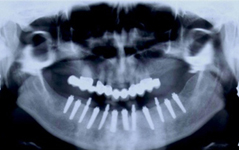

Jsou zavedeny do kosti horní nebo dolní čelisti a umožňují náhradu jednoho, několika či všech zubů pomocí korunek, můstků, které jsou na ně připevněny nebo tvoří podporu pro zubní protézy.

• Zavedení implantátu do kosti čelisti

Klasickým příkladem a indikací pro použití implantátu je ztráta jednoho zubu (v tomto případě v předním – frontálním úseku) v jinak zdravém, nepoškozeném chrupu.

Náhrada jednoho zubu pomocí implantátu je možná také v postranním úseku chrupu. Při ztrátě většího počtu zubů ve frontálním nebo postranním úseku může být mezer uzavřena větším počtem jednotlivých implantátů.

Bezzubá čelist je hlavní indikací pro ošetření pomocí implantátů. Zejména celkové zubní náhrady v dolní čelisti mají velice nízkou stabilitu a držení díky velkému úbytku kosti.